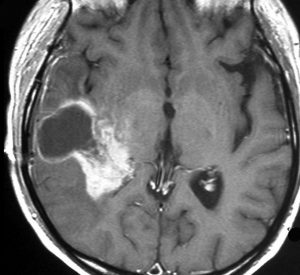

放射線誘発髄膜腫

ジャーミノーマへ44グレイの全脳照射をしてジャーミノーマは治りました。でも,15年後に髄膜腫が発生しました。典型的な放射線誘発腫瘍です。これは取れるので大丈夫!